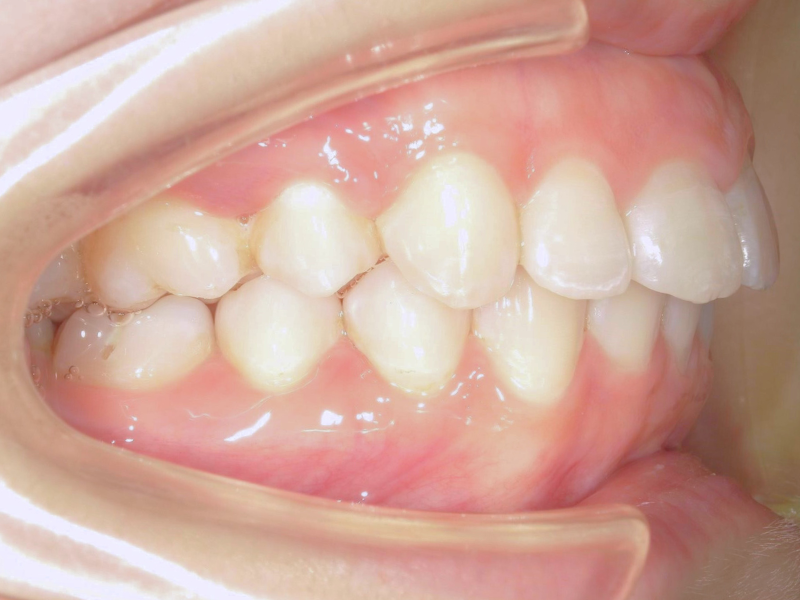

30代、女性、ワイヤー

| 施術内容 | 主訴:噛み合わせが深い 詳細:ワイヤー矯正での歯並び改善 見えなかった下の歯が見えるようになりました◎ |

| 治療期間 | 18ヶ月(3/23現在 治療終了) |

| リスク・副作用 | ■リスク・副作用 ・治療の初期段階では、痛みや不快感が生じやすくなりますが、一週間前後で慣れます。 ・歯の動き方には個人差があるため、予想された治療期間より延長する場合があります。 |

| 費用 | ワイヤー矯正 60万円(税込660,000円) |